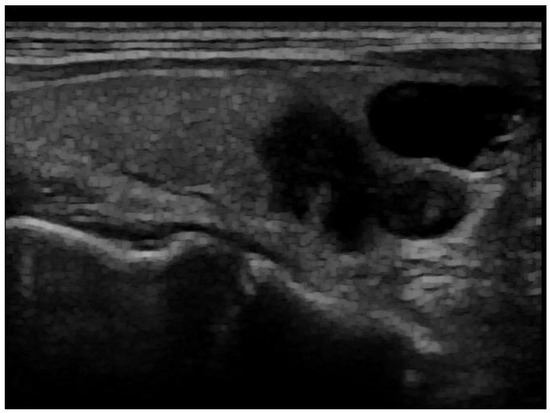

The acquisition settings varied due to differing clinical practices across the hospitals. For our study and analysis, we used retrospective data collected from these diverse settings. Raw images, as in the example shown in Figure 1, were pre-processed to reduce noise and enhance the quality of the input data. Several commonly used image enhancement techniques were performed as follows:

Figure 1. Raw ultrasound image of the thyroid nodule, with noise and artifacts covering part of the textures.